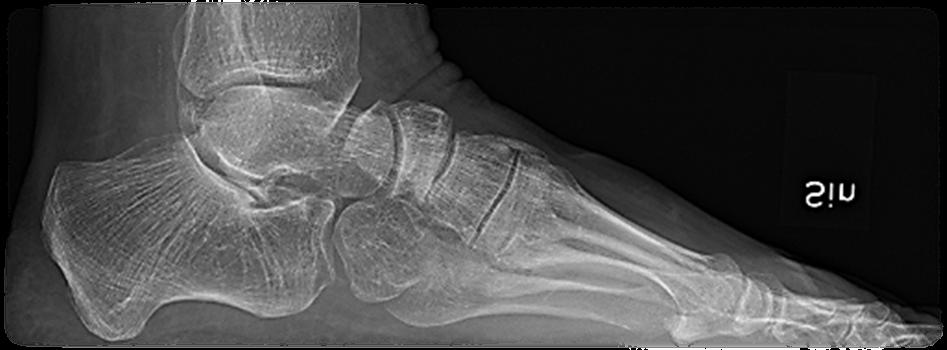

Sannolikt normalt/fysiologiskt hos barn om den är bilateral. Plattfothet undersöks bäst bakifrån när barnet står på hela foten och sedan ställer sig på tå. Då ser man hur bakfoten går från valgus vid belastning till varus vid tåstående. Likaså kan man se att det utvecklas ett längsgående medialt fot valv när barnet ställer sig på tå jämfört med när hela foten belastas. Se bild 1.

Sannolikt. Plattfotheten beror nog mest på flexibla fötter som inte har något strukturellt fel. Observera att det normala är bilateral plattfothet. Unilat eral betyder att en fot är platt, pes plano valgus, eller att den andra är i varus, ibland cavo varus, vilket inte är normalt. Om det finns en tydlig asym metri och fotfelställningen är förvärvad behöver man tänka på möjlig neuropati eller pro cess i spinalkanalen. Se bild 2.

Plattfothet är en felställning i första hand och inte en diag nos. En individuell bedömning av var felställningen sitter och vad den kan bero på behövs. Se bild 3.